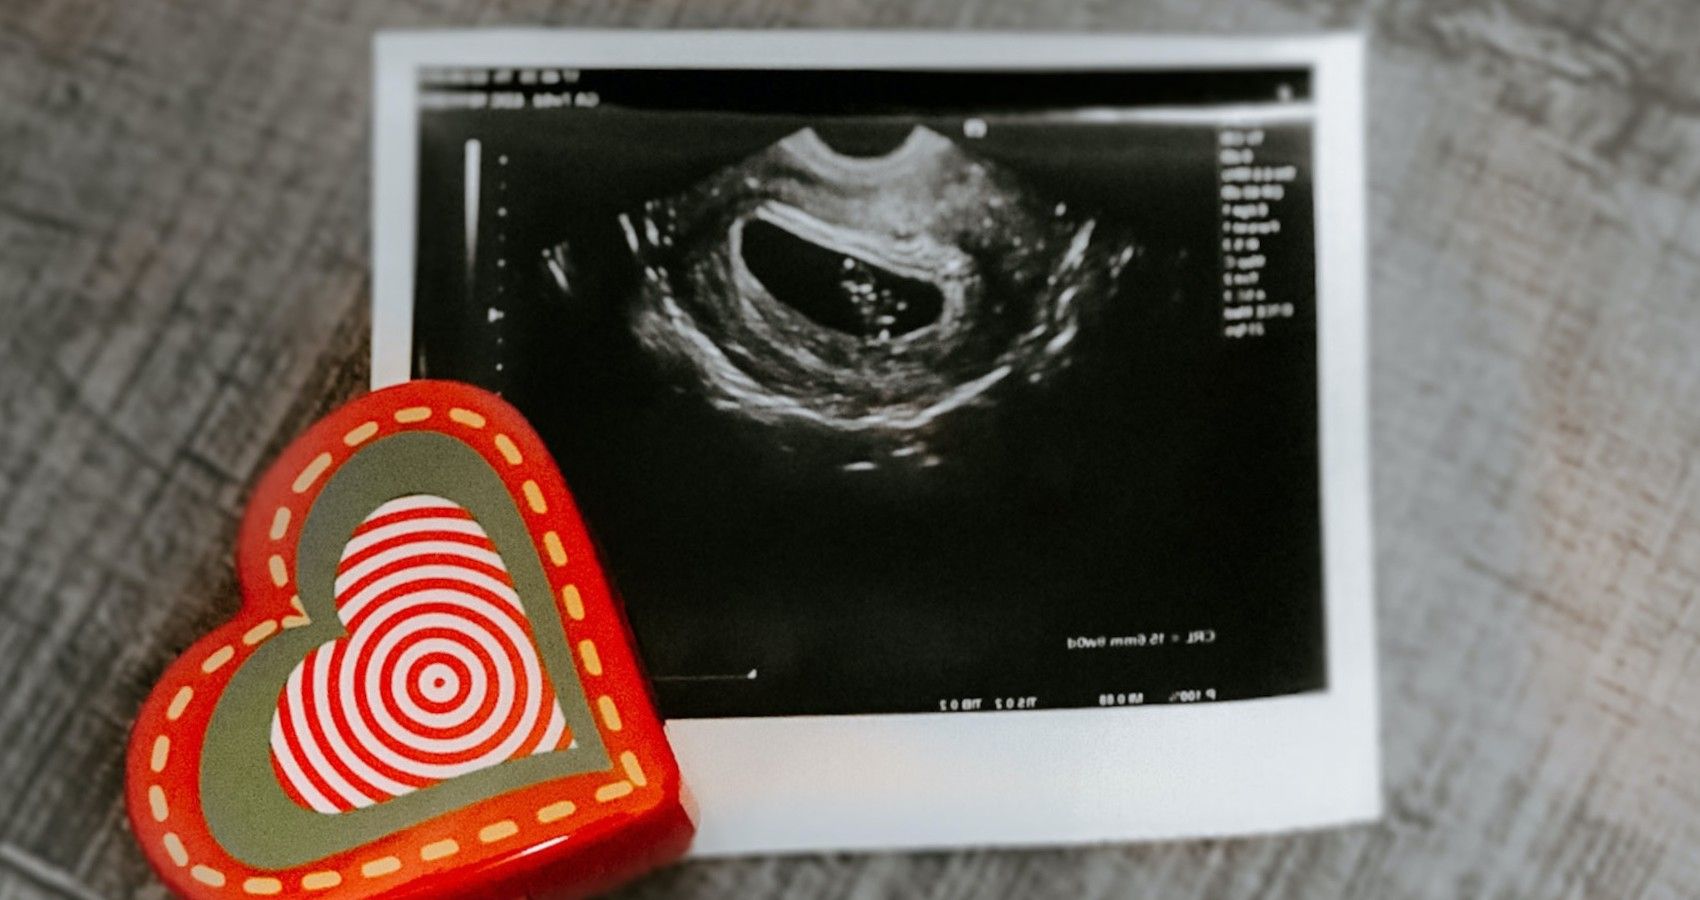

According to and , they are now learning that the risk to an unborn child may be the highest in the first trimester. This may be valuable information for women who have just gotten a positive pregnancy test, or who are about to start trying to conceive.

For the majority of pregnancies, COVID-19 has rarely infected the placenta. is essential for a healthy pregnancy because it is what the baby depends on for oxygen and nutrients. However, rarely does not mean never, and new research has shown that when the virus does infect the placenta, it is typically at the beginning of a pregnancy.